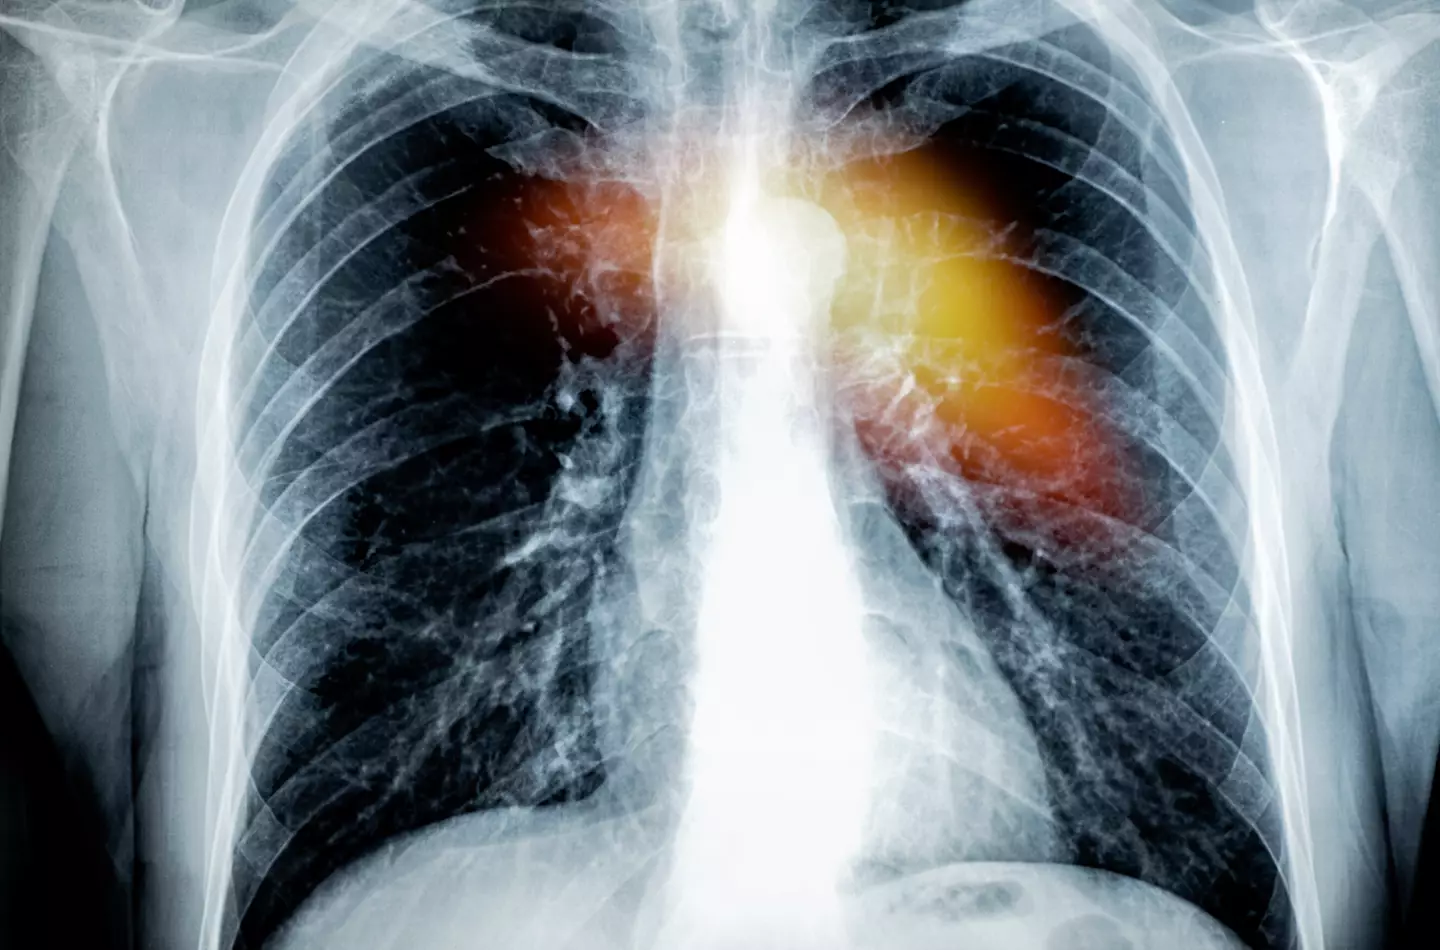

Recently, we shared the story of 22-year-old Kayley Boda, who went through 'one vape a week' until she began coughing up blood, only to be told she was battling lung cancer.

Similarly, teenager LeeRay King was forced to undergo life-saving surgery that saw the removal of his 'shrivelled up, black lungs' at just 17, after he'd puffed on four disposables a week for three years.

Marxen, a LCADC, CCS, went on to discuss a symptom nicknamed 'popcorn lung' (technical name, bronchiolitis obliterans), which overarches many of the most severe cases of vape addiction.

Whilst not cancerous, this condition is caused by a build-up of scar tissue in the lungs, which blocks the flow of air. As such, it can prove fatal.